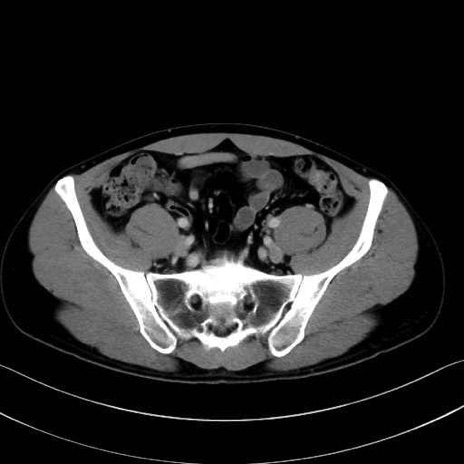

小殿筋 (Gluteus minimus)